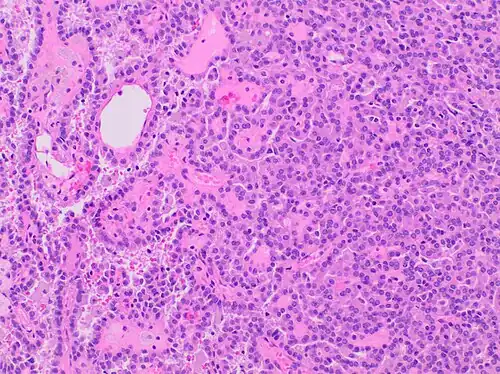

Type 1 PRCC, also known as a renal tumor caused by a genetic predisposition of hereditary papillary renal cancer syndrome, compromises approximately 25% of all PRCCs.[14][15] In the perspective of immunochemistry, it has a profile of strong CK7 and alpha-methyl acyl-CoA racemase (AMACR) expression at most focal CA-IX expression.[16] Histologically, its epithelium is composed of relatively small-sized simple cuboidal cells lined in a single layer.[17] These cells are well-characterized by basophilic cytoplasm.[18] Due to its solid growth, an extremely compact papillary architecture is often observed.[16] Other morphological characteristics include intracellular hemosiderin and foamy macrophages placed inside of papillary fibrovascular cores or psammoma bodies.[19] In general, the nuclei of type 1 PRCC belong to grade 1-2 of the Fuhrman system.[16]

-

A micrograph of type 1 PRCC, illustrating features of small basophilic cells with scarce cytoplasm. A single layer of cells are surrounding the basal membrane.[20] Foamy macrophages are inside of papillary fibrovascular cores. -

Type 1 PRCC, this case being more compact at right.